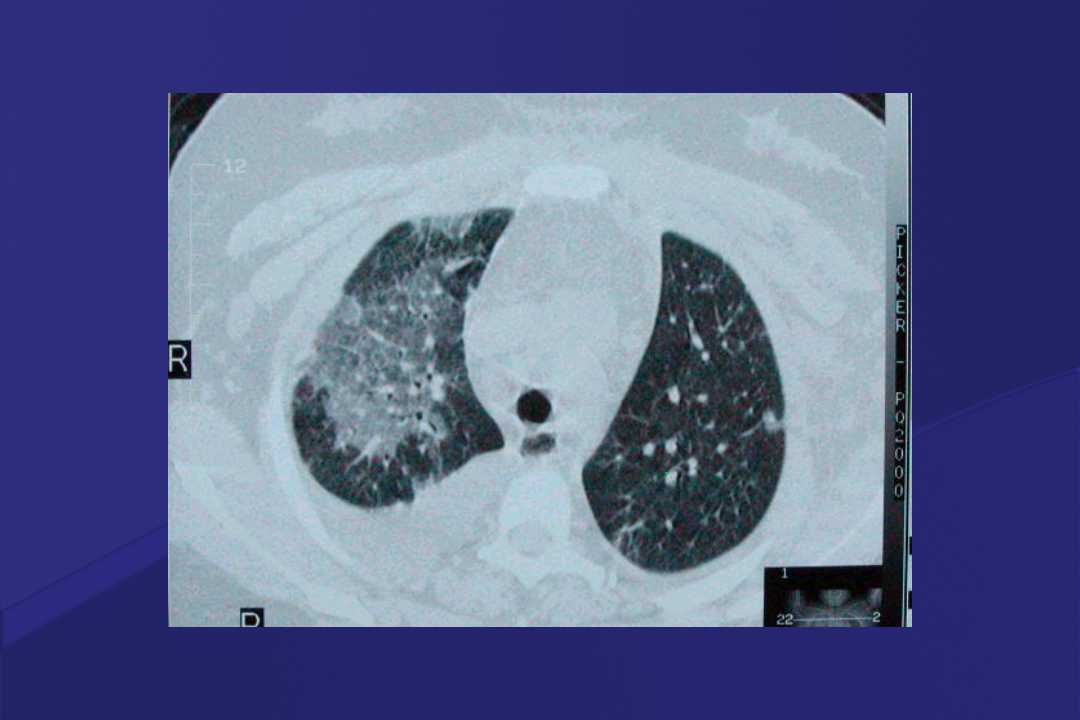

血液疾病患者肺部并发症影像学表现